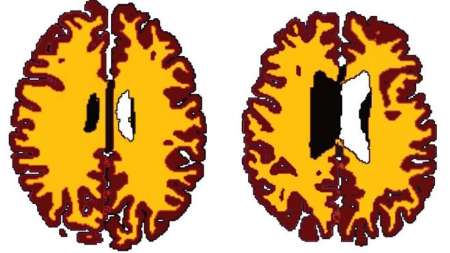

چاقی سبب پیری زودرس مغز می شود و مغز افراد چاق نسبت به هم سن و سالان لاغر 10 سال پیرتر است. حجم ماده سفید مغز به طور طبیعی بر اثر افزایش سن کاهش می یابد؛ ولی چاقی این روند را تسریع می کند. ماده سفید مغز مسئول انتقال اطلاعات است.

نتایج نشان می دهد حجم ماده سفید مغز افراد دارای اضافه وزن نسبت به هم سن و سالان لاغرشان کمتر است و این تفاوت از دوران میانسالی به بعد مشهود تر است. محققان احتمال می دهند مغز با افزایش سن آسیب پذیرتر می شود. این مطالعه همچنین نشان می دهد تاثیر اضافه وزن بر بدن بسیار پیچیده و مضرتر از چیزی است که تا کنون تصور می شد.